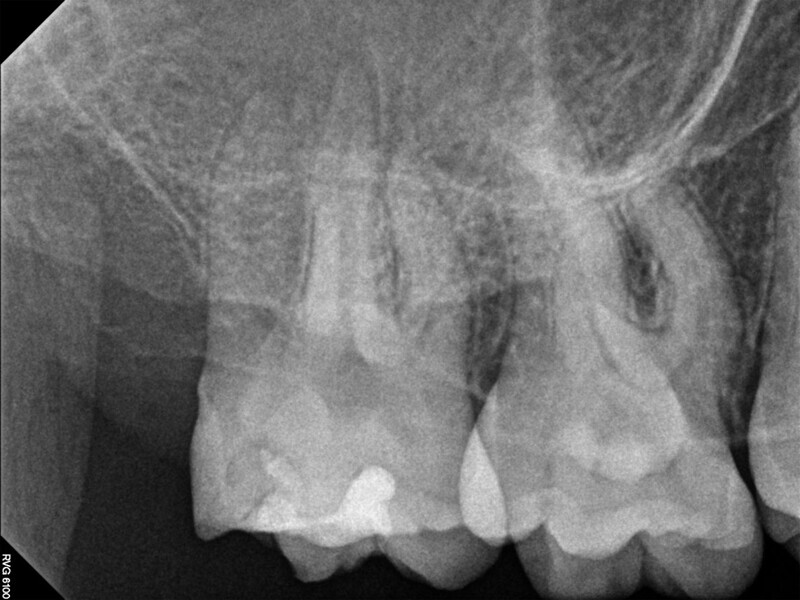

Fig. 17a: Case assisted with CBCT to determine anatomy pre-operatively. Note the multiple cross sections moving apically and the correlation to the 2-D view. Note also the conservative taper in relation to the root width. (Courtesy of Dr. Brett Gilbert)

Fig. 17b: Case assisted with CBCT to determine anatomy pre-operatively. Note the multiple cross sections moving apically and the correlation to the 2-D view. Note also the conservative taper in relation to the root width. (Courtesy of Dr. Brett Gilbert)

Fig. 17c: Case assisted with CBCT to determine anatomy pre-operatively. Note the multiple cross sections moving apically and the correlation to the 2-D view. Note also the conservative taper in relation to the root width. (Courtesy of Dr. Brett Gilbert)

Fig. 17d: Case assisted with CBCT to determine anatomy pre-operatively. Note the multiple cross sections moving apically and the correlation to the 2-D view. Note also the conservative taper in relation to the root width. (Courtesy of Dr. Brett Gilbert)

Fig. 17e: Case assisted with CBCT to determine anatomy pre-operatively. Note the multiple cross sections moving apically and the correlation to the 2-D view. Note also the conservative taper in relation to the root width. (Courtesy of Dr. Brett Gilbert)

Fig. 17f: Case assisted with CBCT to determine anatomy pre-operatively. Note the multiple cross sections moving apically and the correlation to the 2-D view. Note also the conservative taper in relation to the root width. (Courtesy of Dr. Brett Gilbert)